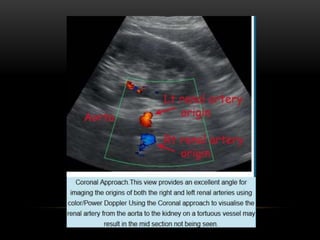

Flank/ Coronal Approach

Roll the patient into a decubitus position to avoid bowel gas and improve

visibility of the renal artery, especially the mid to distal portion.

Flank approach showing the abdominal aorta and origin of both renal arteries.